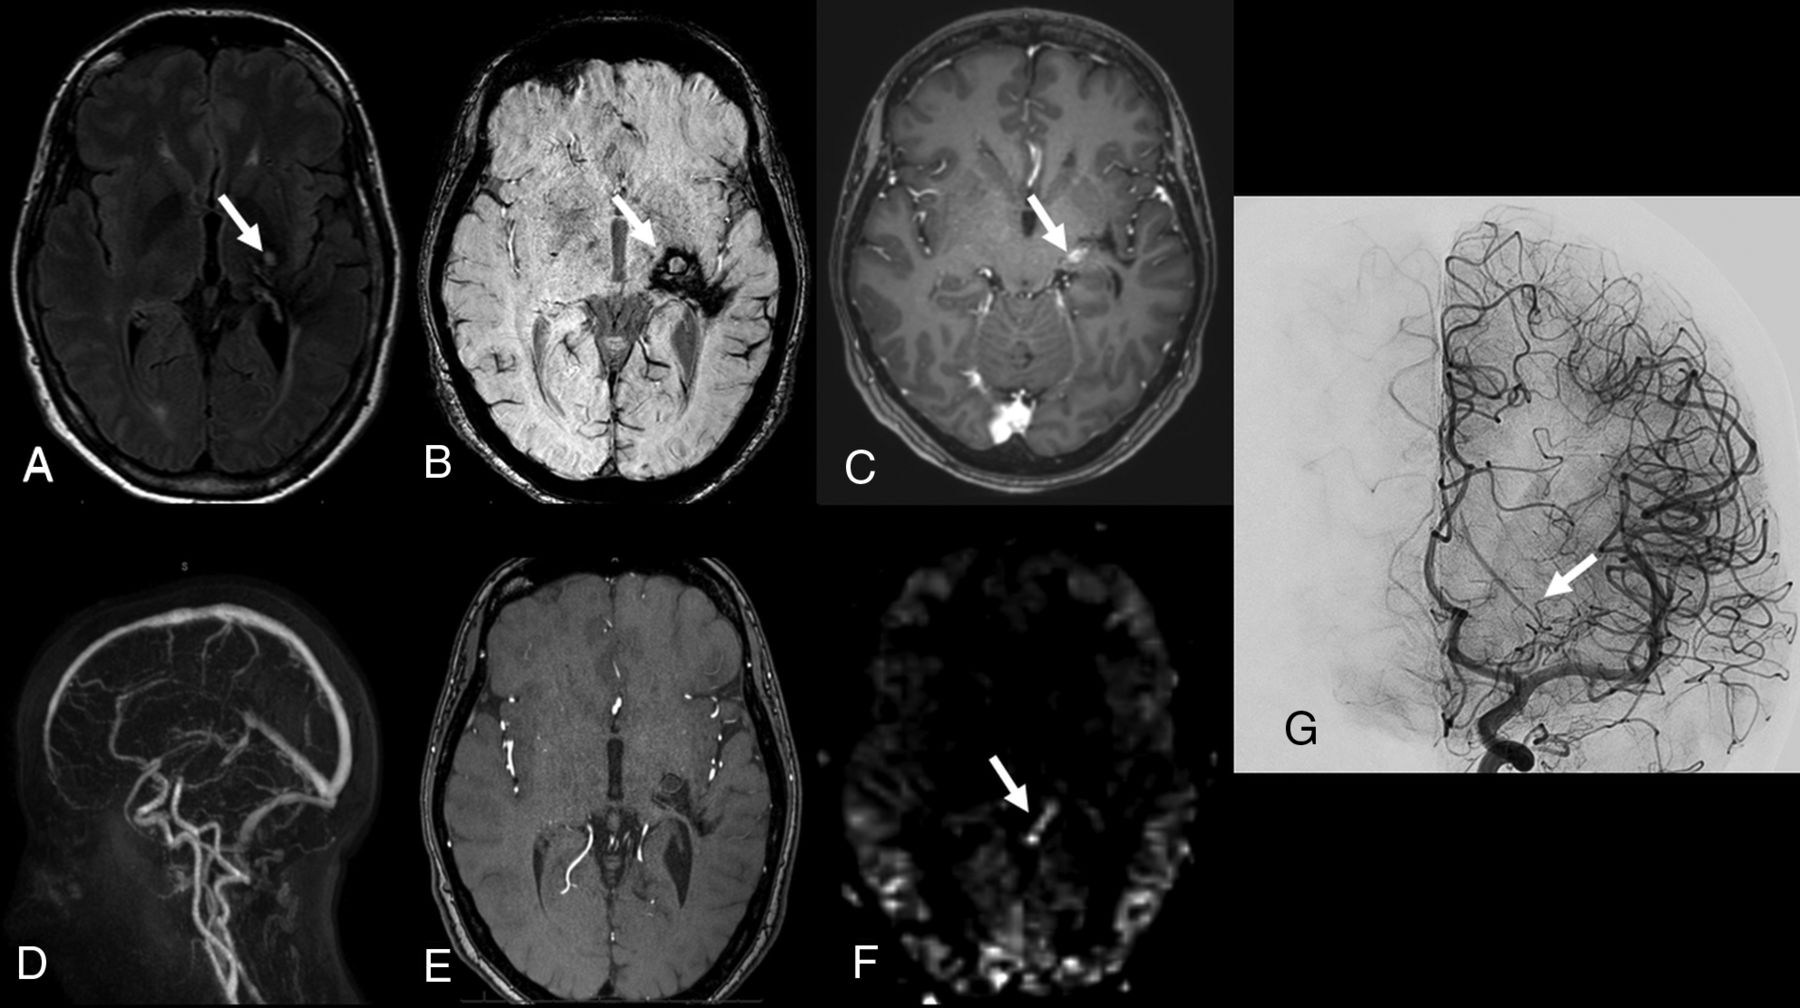

The sensitivity, specificity, positive predictive value, and negative predictive value of MR imaging (all sequences combined) for the detection of residual AVM were respectively 75% (95% CI, 51–91), 100% (95% CI, 63–100), 100% (95% CI, 78–100), and 61.5% (95% CI, 32–86). Individual results are presented in Table 3. In 2 patients, all 3 reviewers reported a BAVM obliteration on MR imaging, whereas DSA demonstrated residual AVS. Of the 6 patients with MR images interpreted as uncertain, DSA revealed residual AVS in 3 patients and nidus obliteration in 3 patients. Fig 1 shows an illustrative example of a residual BAVM demonstrated on both contrast-enhanced MR images and ASL/TOF.

Patient 19. Follow-up MR imaging 2 years after embolization and radiosurgery for a ruptured left parietal brain AVM. A, Axial FLAIR shows hyperintense signal in the left parietal region (arrow) due to radiation injury. B, Axial T2* shows mixed signal intensity related to prior hemorrhage (arrow) posterior to hypointense embolization material (arrowhead). C, Postcontrast 3D T1 GRE axial image shows an enhanced tubular draining vein of a residual BAVM (arrow). D, Sagittal view from 4D contrast MRA with MIP reconstruction shows an early enhanced draining vein on the arterial phase of the angiogram (arrow). E, 3D-TOF with MIP reconstruction shows a residual BAVM (arrow). F, ASL image shows a focal hyperintense signal in the left lateral part of the cingulate gyrus (arrow). G, DSA, lateral view from a vertebral angiogram, confirms a residual nidus (arrow) with deep venous drainage (arrowhead).